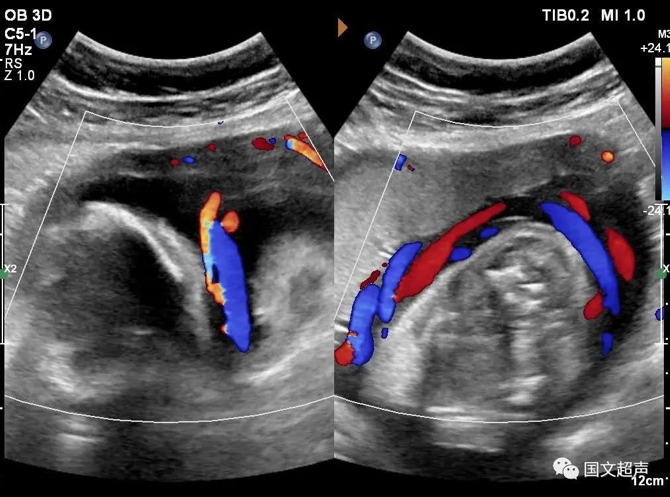

四.關(guān)于臍帶繞頸

臍帶有補(bǔ)償性伸展,纏繞松弛對胎兒影響不大,但如果纏繞過緊可影響胎兒血供,有造成胎心率改變、胎兒缺氧、窒息甚至胎死宮內(nèi)的風(fēng)險。

實(shí)際上影響胎兒預(yù)后的主要因素不在于繞頸的周數(shù),而在于除去繞頸所剩的臍帶長度。如果孕媽媽只繞頸一周但臍帶相對過短,仍可造成不良結(jié)局。

臍帶繞頸的孩子很多,但發(fā)生不良結(jié)局的確占少數(shù),所以不必過度擔(dān)心,只要每天的胎動正常,沒有突然的增多和減少,定期復(fù)查即可。